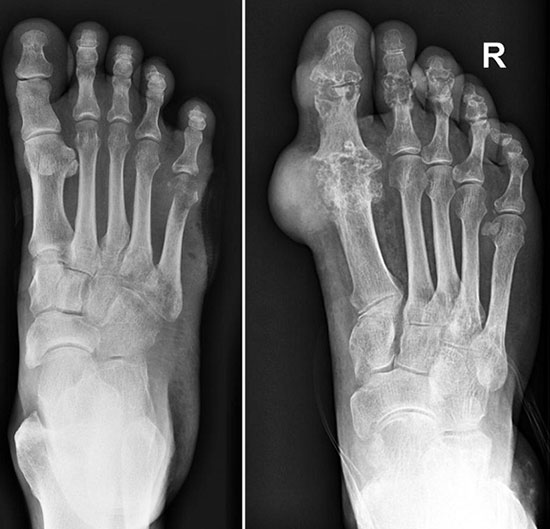

- рентгенографию – поможет обнаружить патологические процессы в суставе;

Рентген здоровой ступни (слева на фото) и пораженной подагрой (справа)